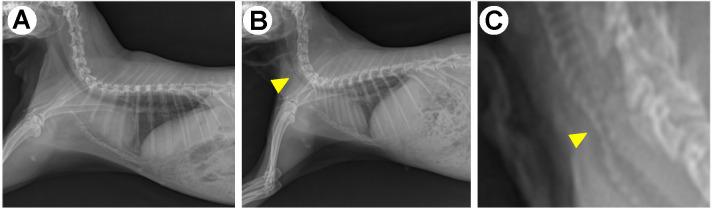

A rabbit model of tracheal collapse for optimal self-expanding metal stents.

Comparison of three different self-expanding metal stents using rabbit models for the treatment of tracheal collapse.

Double-wire woven nitinol stent for treating dogs with refractory tracheal collapse: A case series.